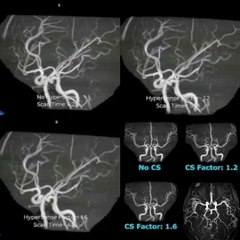

断面図ウォーカー 脳MRI